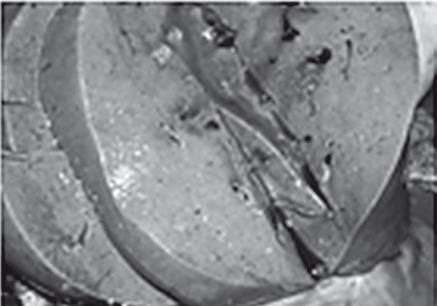

Иллюстрация к книге — Неалкогольная жировая болезнь печени [i_043.jpg]

Индуративный панкреатит